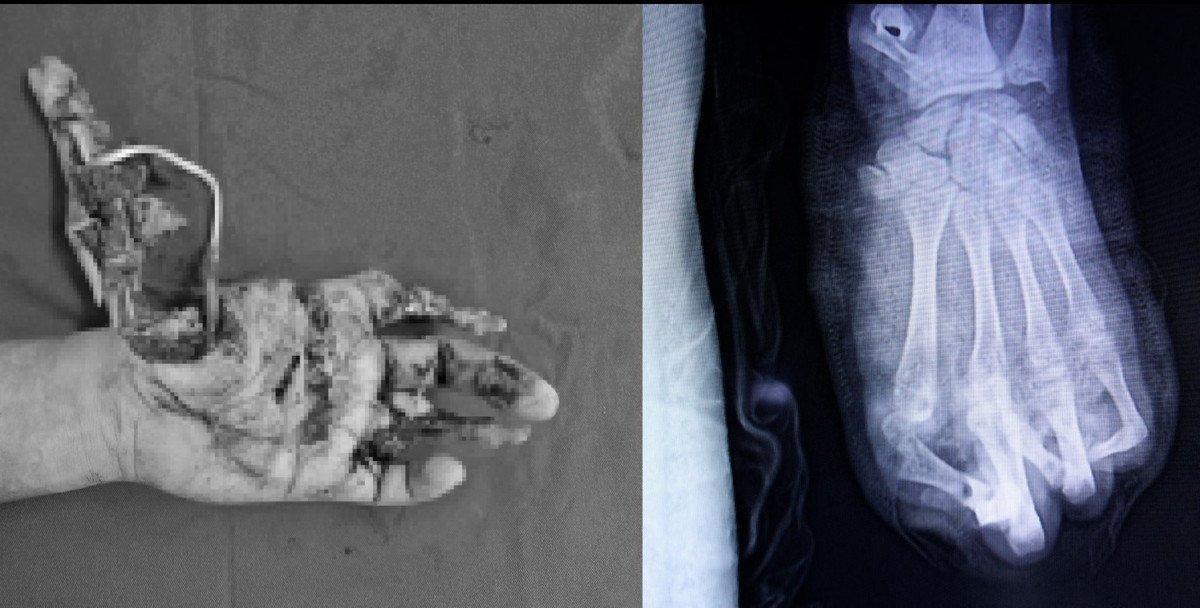

phao-no-3.jpg

Hình ảnh tổn thương thực tế và trên phim chụp - Ảnh BVCC